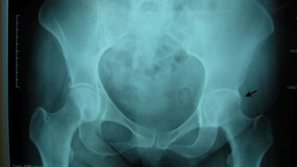

First case was a 47-year-old small female with mechanical impingement, torn labrum, and over 30% delamination of acetabular articular cartilage. There was also concern as to the sizing, that it might be too small for the size 1 ARC stem with a socket size of 46 mm.